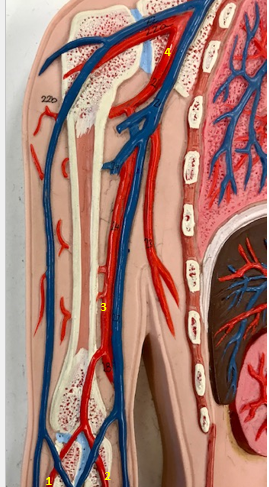

Tunica intima

Name the blue arrow

Lines lumen and release vasoactive chemicals

Function of tunica intima

Venous valves

Name the pink arrow

Prevent backflow of blood

Function of venous valves

Tunica media

Name green arrow

Vasoconstriction and vasodilation

Function of tunica media

Tunica externa

Name the purple arrow

Anchor and bind vessel

Function of tunica externa